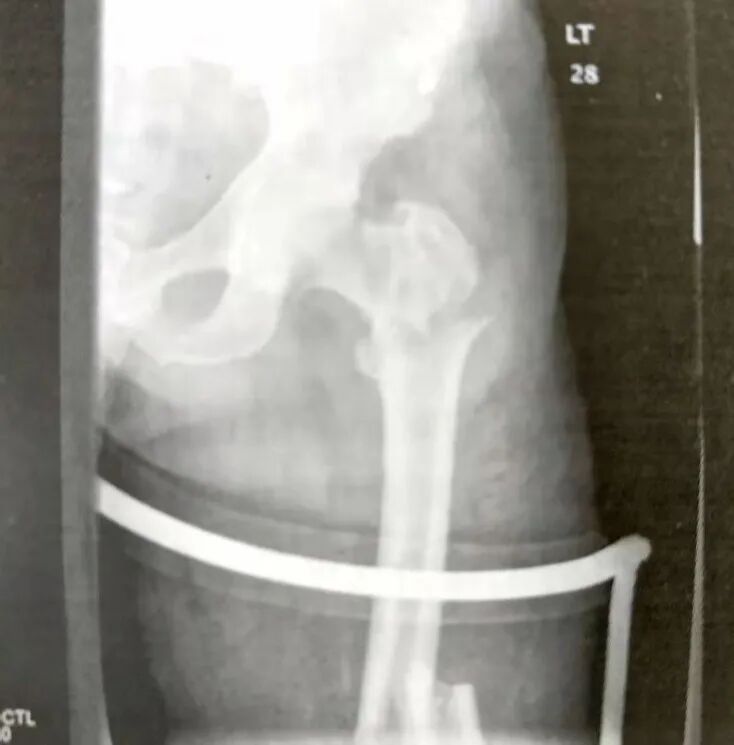

▲ 粉碎性转子下骨折

▲ 复杂的股骨上段骨折累及到转子下